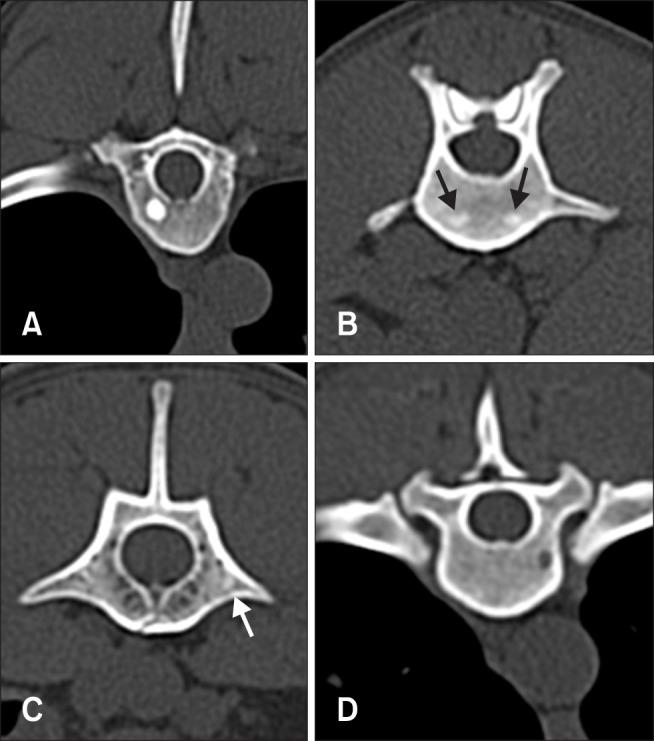

Focal vertebral bone density changes were assessed in vertebral computed tomography (CT) images obtained from clinically healthy dogs without diseases that affect bone density. The number, location, and density of lesions were determined. A total of 429 vertebral CT images from 20 dogs were reviewed, and 99 focal vertebral changes were identified in 14 dogs. Focal vertebral bone density changes were mainly found in thoracic vertebrae (29.6%) as hyperattenuating (86.9%) lesions. All focal vertebral changes were observed at the vertebral body, except for a single hyperattenuating change in one thoracic transverse process. Among the hyperattenuating changes, multifocal changes (53.5%) were more common than single changes (46.5%). Most of the hypoattenuating changes were single (92.3%). Eight dogs, 40% of the 20 dogs in the study and 61.6% of the 13 dogs showing focal vertebral changes in the thoracic vertebra, had hyperattenuating changes at the 7th or 8th thoracic vertebra. Our results indicate that focal changes in vertebral bone density are commonly identified on vertebral CT images in healthy dogs, and these changes should be taken into consideration on interpretation of CT images.

在从无影响骨密度疾病的临床健康犬获取的椎体计算机断层扫描(CT)图像中评估局灶性椎体骨密度变化。确定病变的数量、位置和密度。共回顾了来自20只犬的429张椎体CT图像,在14只犬中发现了99处局灶性椎体变化。局灶性椎体骨密度变化主要见于胸椎(29.6%),表现为高密度(86.9%)病变。除一个胸椎横突出现一处高密度变化外,所有局灶性椎体变化均见于椎体。在高密度变化中,多灶性变化(53.5%)比单灶性变化(46.5%)更常见。大多数低密度变化为单灶性(92.3%)。8只犬,占研究中20只犬的40%,以及13只胸椎出现局灶性椎体变化犬中的61.6%,在第7或第8胸椎有高密度变化。我们的结果表明,健康犬的椎体CT图像上常见椎体骨密度局灶性变化,在解读CT图像时应考虑这些变化。